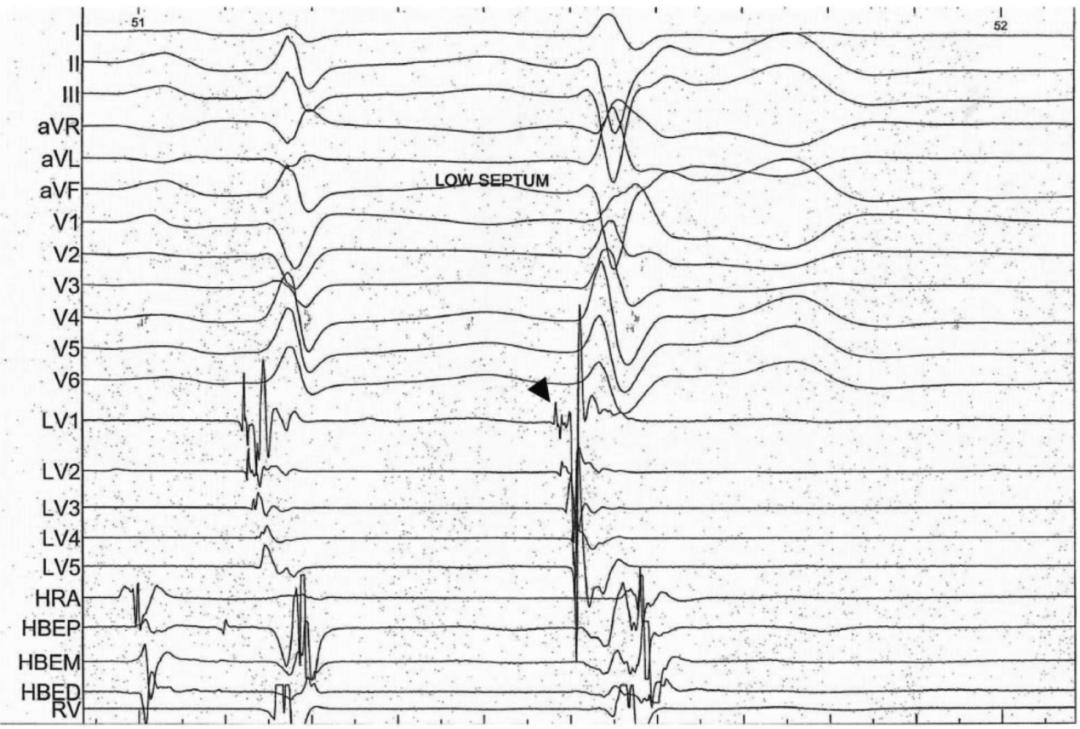

图2 电生理学研究显示,室性早搏起源于后间隔左心室面,之前有不同的浦肯野电位(箭头)

图4分别将四极导管置于希氏束区域、PentaRay高密度标测导管置于左前分支区域进行标测。

第1个搏动为交界性搏动(HV=50毫秒),顺向传导至左前分支(P最早/PEN3-4–QRS间期=12毫秒)。

第2个搏动表现出宽QRS波(124毫秒),电轴指向左上,呈右束支传导阻滞+左前分支传导阻滞形态。希氏束电位埋藏于QRS波中,P最早/PEN11-12–QRS间期=-29毫秒,所以这种异位搏动起源于左后分支的中部。

第3、4、5、6、7和9个搏动,均类似右束支传导阻滞+左后分支传导阻滞的形态(QRS波时限为141-170毫秒);HV间期均为负值,每次收缩前,左前分支区域的浦肯野电位均领先于希氏束电位,这表明在左前分支不同部位起源的异位电活动逆向激活希氏束。

第8个搏动,QRS波非常宽(188毫秒),电轴指向左上,呈左束支传导阻滞形态;看不到希氏束电位(埋藏在QRS之中或之后),P最早/PEN3-4-QRS间期为-82毫秒,这意味着该激动来源于右束支远端。